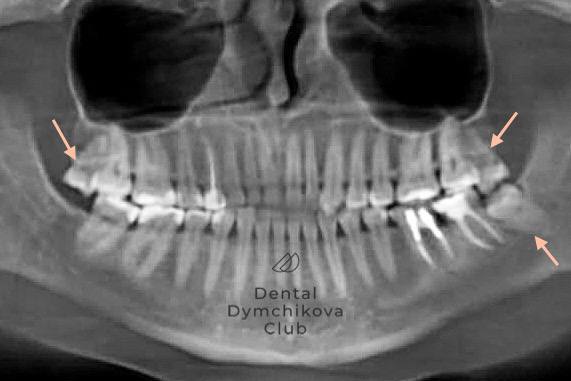

Ортодонтическое лечение, синус-лифтинг, имплантация, протезирование, лечение кариеса

Пациент, 33 года.

Жалобы: на неровные зубы, желание поменять мосты на задних зубах.

Исходные данные: скученность зубов, наличие кариесов, недостаток кости по высоте для установки имплантатов.

Лечение:

1) санация полости рта (лечение кариеса),

2) ортодонтическое лечение (брекеты, минивинты),

3) синус-лифтинг и имплантация в области отсутствующих зубов на этапе ортодонтического лечения,

4) протезирование зубов и имплантатов коронками.

Срок лечения: 2,4 года.

Доктора: Ефимова Дарья Юрьевна, Дымчикова Анна Вавиловна, Лебедева Адиса Тумэновна.